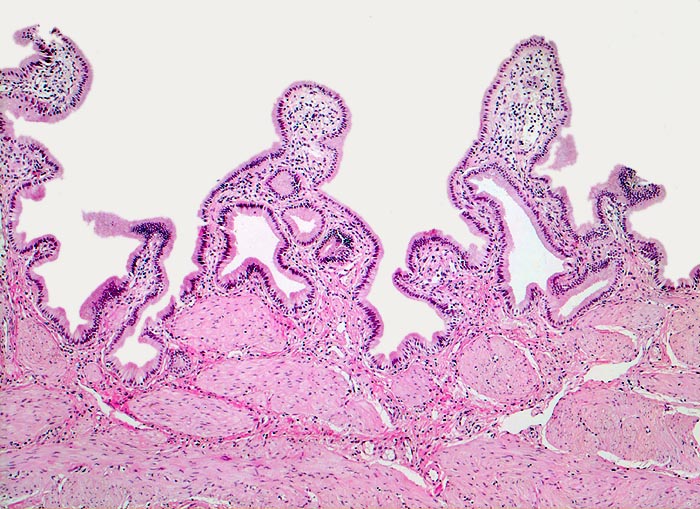

Normale Gallenblase

Gallenblase

Die Gallenblasenschleimhaut bildet unregelmässige Falten, die bedeckt sind von einem hochzylindrischen Epithel. Unterhalb der Mukosa eine dicke Schicht glatter Muskulatur. Anders als in anderen Hohlorganen des Gastrointestinaltrakts fehlen eine Lamina muscularis mucosae und eine Submukosa.

Histologie

50